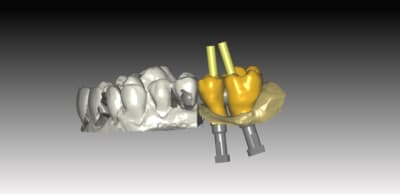

exemple de réalisation ..

sur ce cas pas de base titan, pas nécessaire because branemark , exagone externe base large ,bonne surface d'assise

Je posterais d autre cas sur du nobel activ (avec ambase ) strauman BL et NBreplace

faites l'économie d'un pilier , et appréciez le confort du transvissé :):)